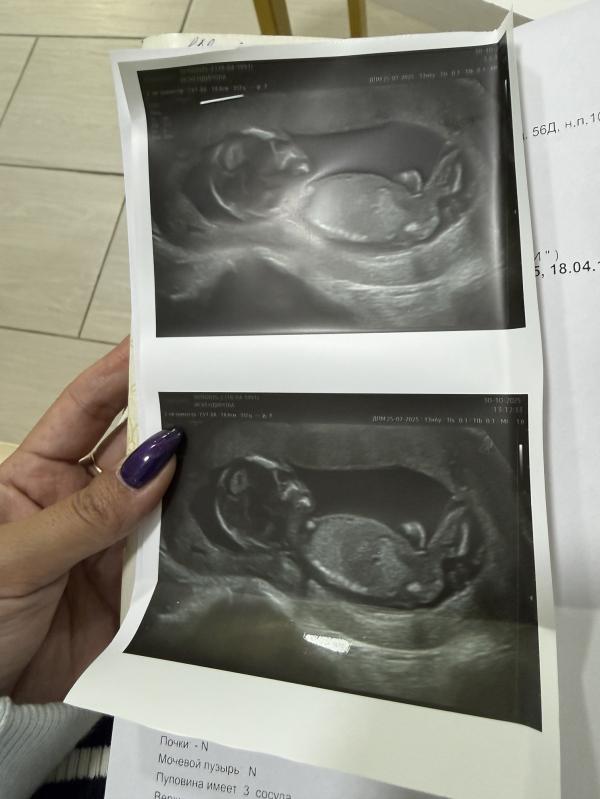

Сходила на узи, сказали что девочка

Очень хотела сына, немного расстроилась… но самое главное, что малыш здоров 🙏

Ну и срок еще маленький, возможно еще изменится… бывает же такое… просто я сон видела и сама чувствую что мальчик…